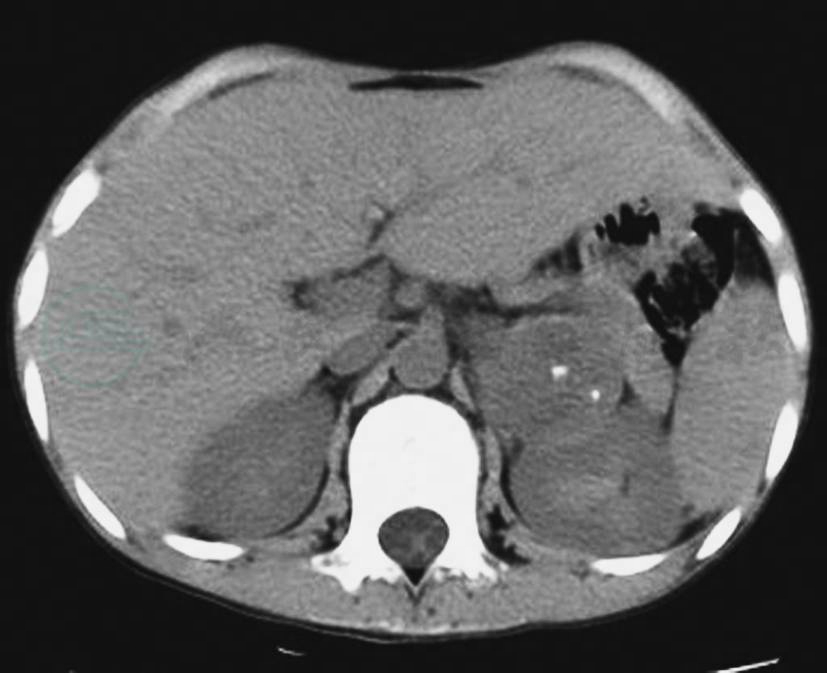

图10左侧肾上腺恶性嗜铬细胞瘤

CT平扫示左侧肾上腺区域巨大瘤体,其内囊变坏死较明显,并见粗大钙化